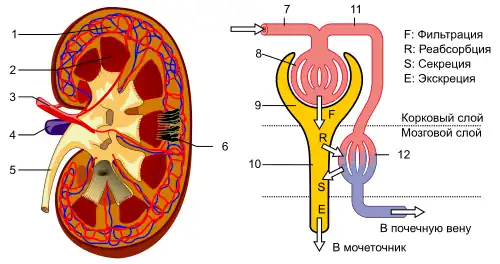

Почки млекопитающих, как и у других наземных позвоночных, тазовые (метанефрические). Они обычно имеют бобовидную форму и располагаются в поясничной области, по бокам позвоночника. В наружном корковом слое каждой почки располагаются нефроны, в почечных клубочках которых происходит фильтрация плазмы крови[166] и образуется моча, стекающая затем по мочеточникам в мочевой пузырь. Из него моча по мочеиспускательному каналу выходит наружу[167].

Почки регулируют количество воды в организме и выводят из него токсичные продукты обмена веществ. Конечными продуктами белкового обмена являются мочевина и мочевая кислота. Мочевина образуется в печени из аммиака, а мочевая кислота — продукт распада пуринов[168]. При этом у млекопитающих мочевина по содержанию в моче резко преобладает над мочевой кислотой (у рептилий и птиц соотношение обратное). Помимо почек, определённую роль в выделении играют потовые железы[169] и лёгкие, а также печень.

Почки млекопитающих также являются основным органом, участвующим в осморегуляции. Они могут выделять гипотоническую мочу при избытке воды и осмотически концентрированную — при её дефиците[170].